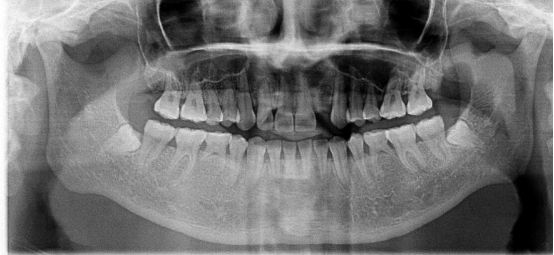

不連續(xù)性牙缺失修復(fù)案例

53歲的周女士家住福州晉安,由于患有嚴(yán)重的牙周炎導(dǎo)致牙齒沒剩下幾顆了。

“這邊缺一顆,那邊缺幾顆,這咬東西也太不得勁了,有牙齒跟沒牙齒一樣?!敝芘可钪例X缺失的痛苦,但是卻因為經(jīng)濟的原因一直拖延沒有進行牙齒修復(fù):“做牙齒多貴了,一顆就幾萬塊哪里舍的?!?

錢雖然重要但缺失牙確實痛苦。而近期周女士又湊巧在報紙上看到科爾口腔的“敬業(yè)福”公益活動的消息,一顆牙齒可以免費領(lǐng)取4000元的種植牙紅包,優(yōu)惠力度之大前所未有,種植5顆還可以省下幾萬塊。

周女士來院與劉斌元教授進行交流后,劉斌元教授表示:“周女士缺失的牙齒是非連續(xù)性的,因此要種上好幾顆。牙齒缺失千萬不可掉以輕心,長時間缺失牙齒可造成牙槽骨萎縮,還會影響相鄰牙齒健康狀況”